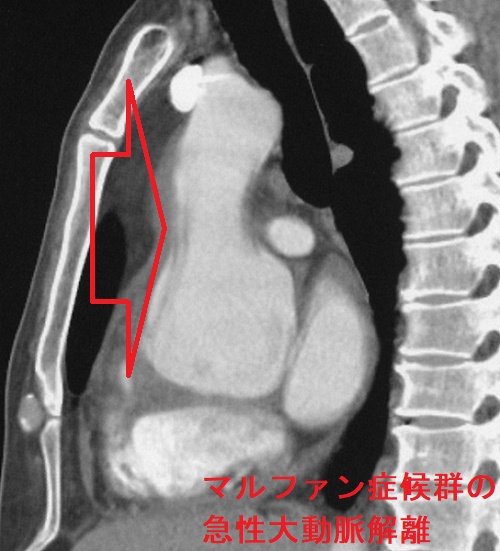

マルファン症候群(marfan syndrome:MFS)は、常染色体優性遺伝性の結合組織異常。フィブリリン-1(fibrillin-1)をコードするFBN1遺伝子やTGF-β 受容体遺伝子の突然変異が原因で、過剰TGF-βの臓器沈着からコラーゲン形成障害が生じます。

マルファン症候群の身体的特徴として、高身長で四肢の指が長い、胸郭の変形、眼の水晶体亜脱臼などがあります。

マルファン症候群で特に問題となるのが大動脈壁の脆弱性で、

- 大動脈弁輪拡張による大動脈弁閉鎖不全症(AR)

- 大動脈瘤、急性大動脈解離がおきると命にかかわる

通常の急性大動脈解離は60歳以上の高齢者に多いが、マルファン症候群では20歳-30歳代に発症することが多い。激しい運動はマルファン症候群の脆弱な動脈壁を破綻させるため禁忌。

マルファン症候群の急性大動脈解離 胸部造影CT 水平断像;矢印はflap